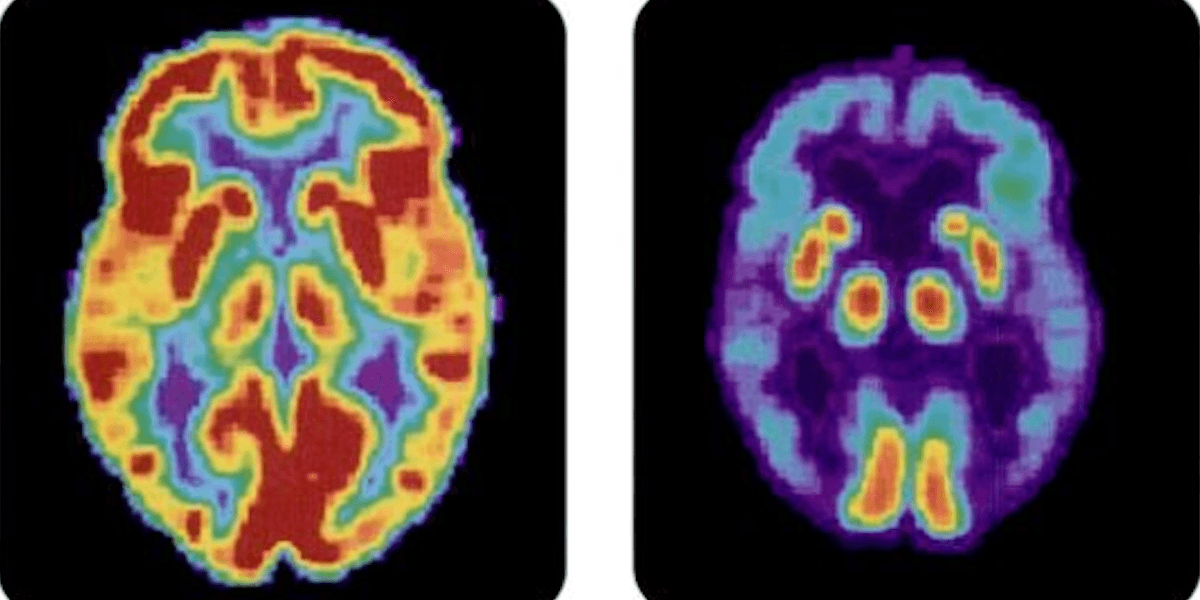

Demenssjukdomen Alzheimers kännetecknas av kognitiv försämring och påverkar de regioner av hjärnan som är involverade i våra tankar, vårt minne och vårt språk.

Forskare tror att Alzheimers orsakas av en onormal uppbyggnad av vissa proteiner i och runt hjärncellerna men det är inte helt klart vad som utlöser detta.